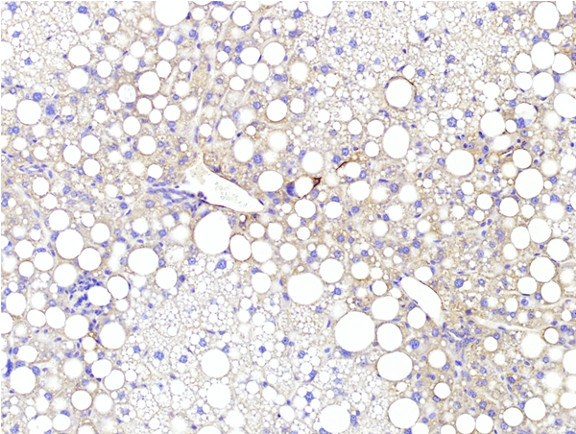

Figure 6: Histopathology for C57BL/6NTac mice placed on D09100310 diet (MASH B6NTac) or kept on chow diet (Control B6NTac) from 6 weeks of age. Animals were on diet for 27, 35 or 53 weeks. Hematoxylin and eosin (H&E) staining illustrates morphological changes including steatosis and infiltration of immune cells. Activated HSCs were identified in liver sections by using a rabbit polyclonal antibody to alpha-smooth muscle actin (a-SMA) (1:500 dilution; ab5694; Abcam, Cambridge, MA) which was detected by an anti-rabbit IgG embedded polymer with embedded horseradish peroxidase and visualized with 3,3′-diaminobenzidine (DAB) chromogen (Agilent, Carpentaria, CA). Hepatocellular lipid droplets were identified by visualization of the lipid-binding protein adipophilin known to be expressed in steatotic livers. Sections of livers were probed using a rabbit polyclonal anti-adipophilin antibody (1:200 dilution; NB110-40877, Novus Biologics, Littleton, CO) which was detected by an anti-rabbit IgG embedded polymer with embedded horseradish peroxidase and visualized with 3,3′-diaminobenzidine (DAB) chromogen (Aligent, Carpentaria, CA). Picrosirius red (PSR) staining illustrates collagen I and III fibers and is used to measure fibrosis. The same individual MASH or control animal is shown for all four stains in a particular time point. Different individual animals were used for each time point (i.e. data is not longitudinal by animal). Histopathology services provided by IDEXX BioAnalytics.